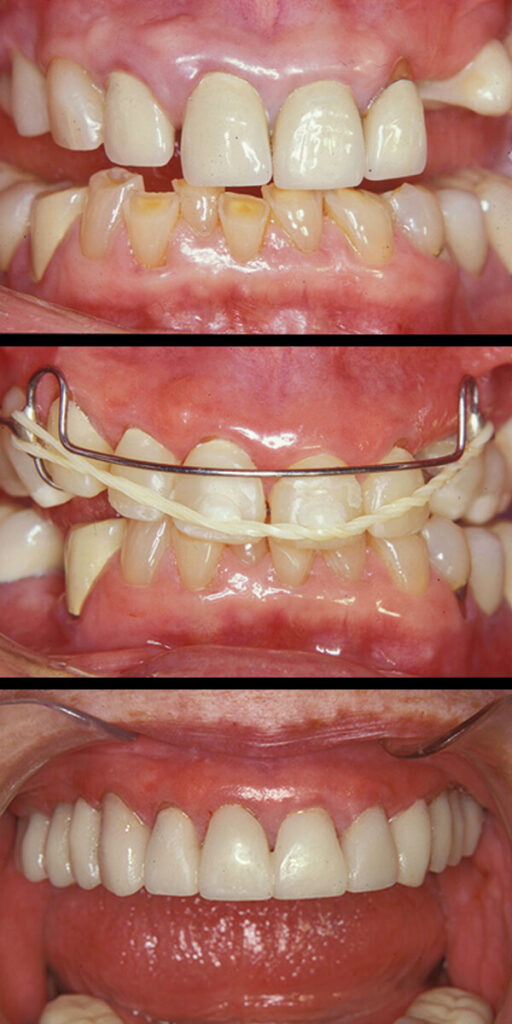

Gummy Smile

A “Gummy Smile” is a condition in which there appears to be too much gum showing when smiling and teeth that look “too short”. This is known as Altered Passive Eruption. A gummy smile is quite unsightly and can be embarrassing because it looks like you have “baby teeth”.

In most cases the condition can be easily treated in one visit by “sculpturing and reshaping” the soft tissue around the involved teeth, revealing more of your natural tooth that has been “hiding” underneath.

As one can see in the following cases, treatment can yield a dazzling result, leaving our patients with “something to smile about”!